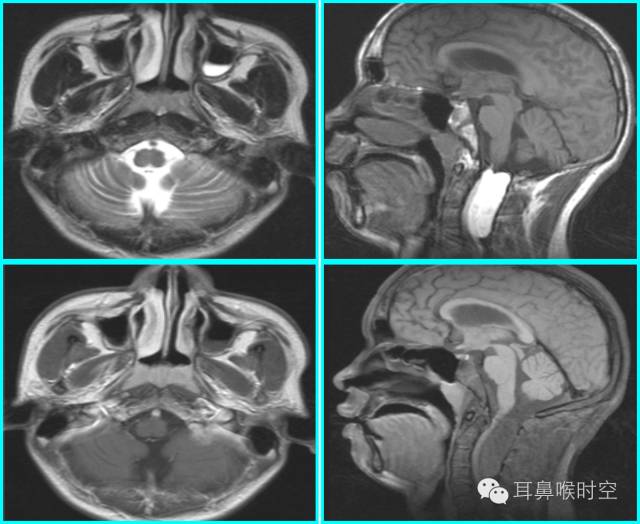

采用SE 序列矢状面T1WI

选择正中矢状面,分别测量两条径线(图1、2)

N 线:即从蝶骨体2枕骨斜坡的软骨结合部后缘(O点)至硬腭与软腭上缘交界处的连线N

A 线:过O点沿枕骨斜坡下缘作延长线L,取腺样体下缘最凸点作L线的垂直线。

A/N比:分别测A、N值,计算A/N 比

正常组镰刀形(图4)、刀鞘形(图5)为主

镰刀形、刀鞘形,腺样体厚度较薄,下缘凹陷或平直,但均不下凸

肥大组子弹形(图6)、山丘形(图7)为主

肥大组:子弹形、山丘形,腺样体饱滿、下凸,象山丘样突出。在冠状面上腺样体表现为“马鞍形”和“倒置梯形”。

解剖结构:在MRSET1WI 鼻咽部正中矢状面图像上,由于采取薄层断面成像

可以直观显示腺样体本身

清晰显示蝶骨体与枕骨斜坡之间的软骨接合部、鼻后孔间隙、鼻甲、硬腭与软腭上缘的交界面、软腭、会厌软骨等结构

易于测量:非常容易画出A 线及N 线,及测量PAS,了解鼻后孔间隙、鼻甲大小、软腭厚度及后突程度

MRI表现:

多方位检查

有利于显示肥大的腺样体

呈等T1、长T2信号

增强时可强化